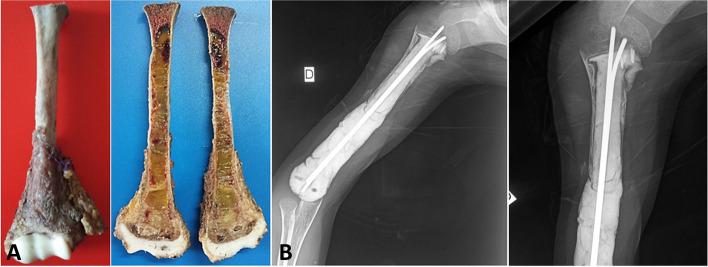

We retrospectively reviewed 11 cases of high-grade malignant bone tumors in children aged 4 to 16 years, who were treated with chemotherapy and tumor resection while preserving partially the adjacent periosteum. Tumors were located in the lower limb in eight cases; three tumors were in the humerus. The mean length of the bone defect after resection was 15.8 cm (range, 6-34.5 cm). Reconstruction was provided by non-vascularized autograft in eight cases (lower limb) and polymethyl methacrylate spacer in three cases (upper limb). Patients were followed up for a mean of 71 months.

At the last follow-up, no patients had local recurrence. Three patients were dead because of metastasis. Bone union was good in time and quality in all children who had bone autografting. In cases of PMMA reconstruction, there was periosteal bone formation around the spacer. According to the MSTS functional score, patients with lower limb localizations had a mean score of 27.75 points and patients with upper limb localizations had a score of 24/30.